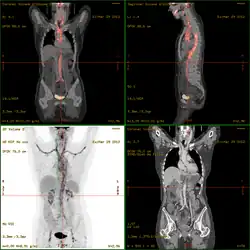

2-FDG wird in der PET für die Diagnose,[24] Staging (Stadienbestimmung), Therapieeinstellung und Therapiekontrolle verwendet. Man spricht in diesem Zusammenhang auch oft von der „FDG-PET“. 2-FDG ist als Diagnostikum eine außerordentlich nützliche und vielfach bewährte Verbindung. Die Anwendung hat einen rein diagnostischen Hintergrund. Genutzt wird dabei die bei der Paarvernichtung (Annihilation) von Positron und Elektron entstehende Vernichtungsstrahlung. Bei der Annihilation entstehen zwei hochenergetische Photonen, die eine Energie von 511 keV haben und in einem Winkel von 180 Grad zueinander, ausgesandt werden. Für die Therapie (Strahlentherapie, in diesem besonderen Fall würde man von einer Endoradiotherapie sprechen) sind die für die Diagnostik genutzten Gammaquanten nicht geeignet.

Für die FDG-PET gibt es drei Hauptindikationen für die Untersuchung von Patienten mit onkologischen Erkrankungen:[19] die Differenzierung zwischen benignen oder malignen (gutartig oder bösartig) Tumoren, das Tumorstaging bezüglich der Lymphknoten und Fernmetastasen sowie die Differenzierung Narbengewebe/vitales Tumorgewebe (Rezidiv, residueller Tumor). Die FDG-PET wird in der Onkologie zur Untersuchung von Lungenkrebs, dem kolorektalem Karzinom, Speiseröhrenkrebs, Magenkrebs, Kopf-Hals-Karzinom, Gebärmutterhalskrebs, Eierstockkrebs, Brustkrebs, dem malignen Melanom und den meisten Arten von Lymphomen eingesetzt.[31] Insbesondere sehr langsam wachsende Tumoren weisen in der Regel keine wesentlich erhöhte FDG-Aufnahme aus. Eine FDG-PET-Untersuchung ist dann meist nur in Ausnahmefällen sinnvoll.[19] Dazu gehören Prostatakarzinome, differenzierte neuroendokrine Tumoren (z. B. Karzinoid), bronchoalveoläre Karzinome, niedrig maligne Non-Hodgkin-Lymphome, niedrig maligne Hirntumore (Astrozytom II, Oligodendrogliom II) und das Leberzellkarzinom (vor allem höher differenzierte Formen). Entzündungen bzw. Heilungen zeigen neben dem Tumorgewebe ebenfalls eine erhöhte Stoffwechselaktivität und somit eine erhöhte FDG-Aufnahme. Eine Untersuchung zur Differenzierung beispielsweise von Abszessen und Tumorgewebe, Sarkoidose, Bronchialkarzinomen usw., kann deshalb mit 2-FDG kaum sinnvoll durchgeführt werden.[19]

Es wird als In-vivo-Diagnostikum in der Medizin verwendet. Der natürliche Zucker und sein Mimetikum FDG werden von den Zellen des menschlichen Körpers zunächst in gleicher Weise aufgenommen, aber anschließend unterschiedlich verstoffwechselt. Dies hat eine bezweckte Anreicherung des Diagnostikums in bestimmten Körperzellen zur Folge. In den zu untersuchenden Geweben wird die Konzentration des FDG-Tracers tomographisch erfasst. Auf diese Weise werden Normabweichungen lokalisiert und damit Hinweise auf organische Funktionsstörungen erhalten. Mit dem Radionuklid Fluor-18 (18F) markierte FDG ist das am häufigsten verwendete Radiopharmakon in der Positronen-Emissions-Tomographie. Strahlungsfreie FDG wird experimentell in der Magnetresonanztomographie erprobt. Als Therapeutikum ist FDG nicht zugelassen.